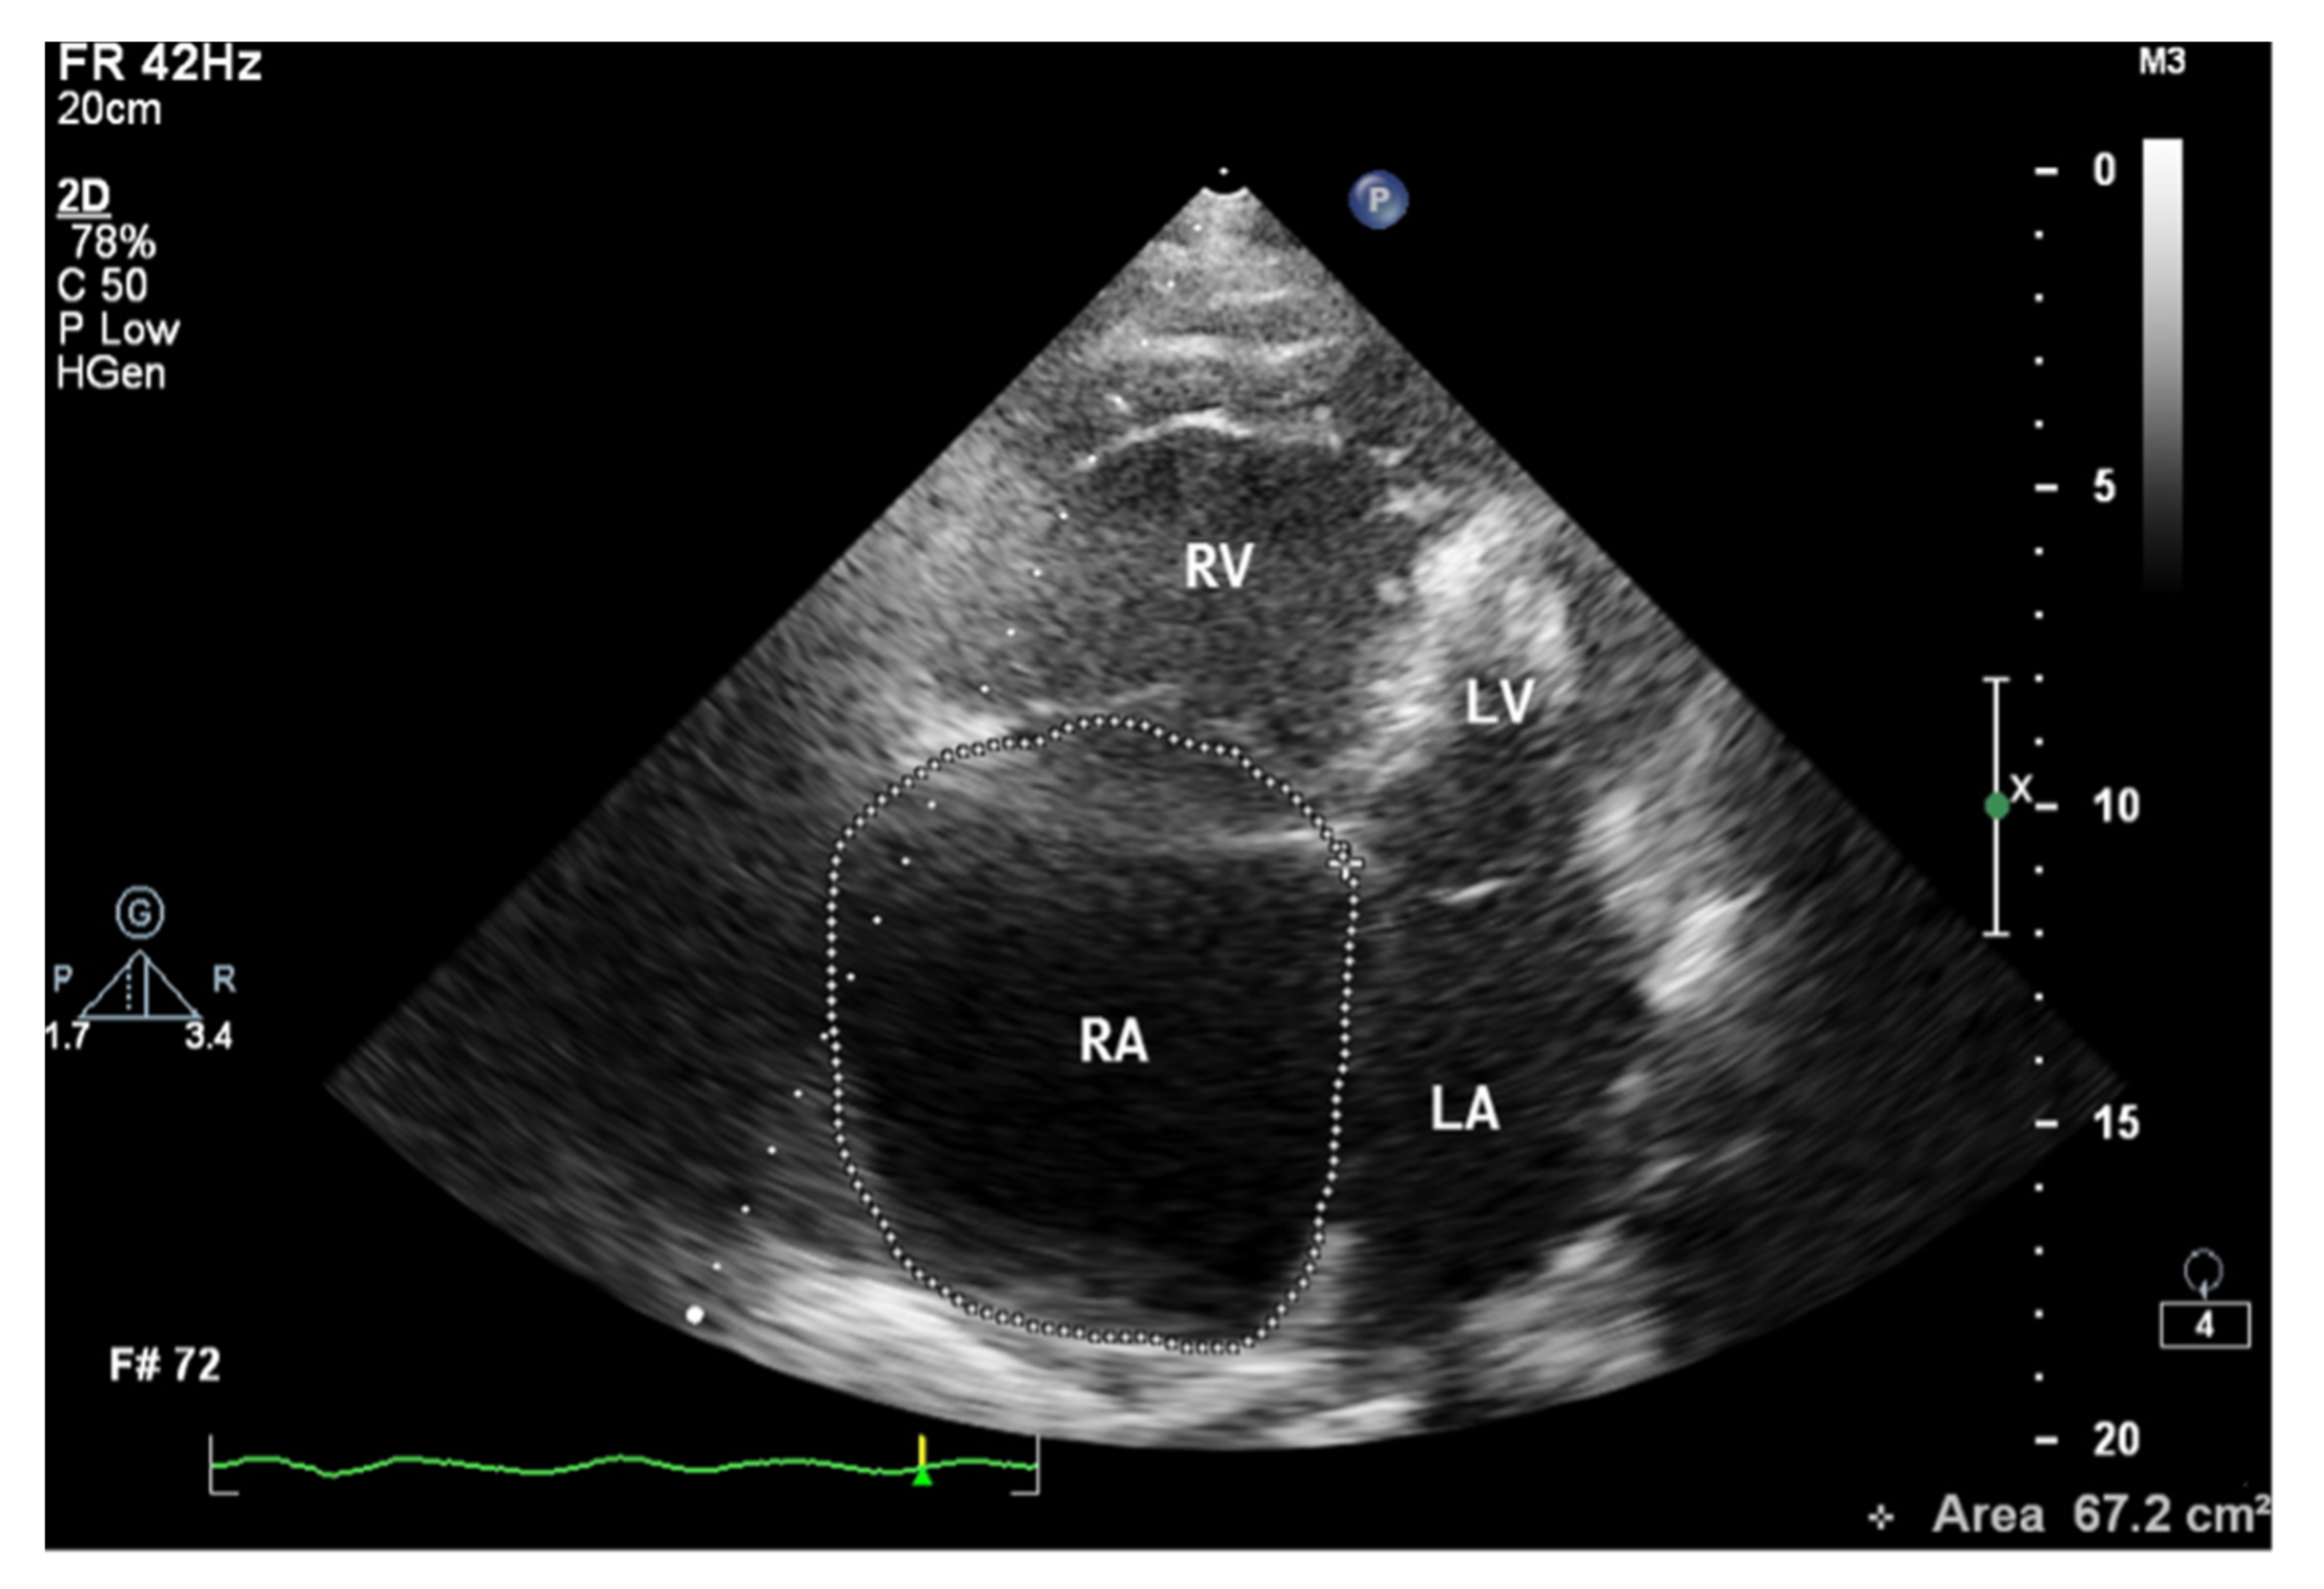

When assessing the right heart′s size, the dimensions of the right atrium (RA) should not be overlooked (Figure 6). The linear dimension of RA should be marked in the 4CH view, perpendicular to the long axis of the heart (Figure 7) [23]. However, more valuable in terms of clinical significance is the RA volume, also measured in the 4CH view [23]—an RA area greater than 18 cm2 indicates enlargement and is one of the most common echo abnormalities found in PAH patients [24].

Figure 7.

Enlarged right atrium with an area of 67.2 cm2. 2D-TTE, 4CH view. 2D-TTE: two-dimensional transthoracic echocardiography; 4CH: four-chamber.